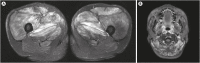

As more individuals were coronavirus disease 2019 (COVID-19) vaccinated, unexpected side effects appeared. Herein, we present the case of a 30-year-old man with myopathy in both extremities after the second dose of the Pfizer-BioNTech (BNT162b2) COVID-19 vaccine. Symptoms, swelling and pain, started from the proximal upper and lower extremities and extended to the distal parts. Although he underwent massive hydration, the muscle enzyme level continuously increased. He complained of dysphagia and dysarthria. Microscopically, muscle biopsy showed multifocal or scattered macrophage infiltration and degenerated myofibers. In contrast to general myopathy including inflammatory myositis and rhabdomyolysis, vaccine-induced inflammatory myositis shows a prolonged increase in muscle enzyme levels and multifocal macrophage infiltration with necrosis of the muscle fibers. Symptoms improved with glucocorticoid and immunosuppressive treatment. If vaccinated individuals experience severe and continuous muscle pain and swelling, clinicians should consider vaccine-induced inflammatory myositis, measure the muscle enzyme levels, and perform muscle biopsy for a definite diagnosis.